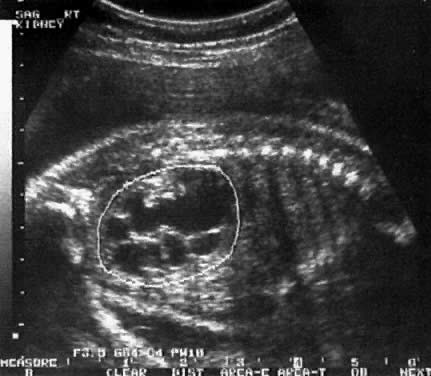

Bebeklerde Böbrek Genişlemesi Down Sendromu

Bebeklerde Böbrek Genişlemesi Down Sendromu.